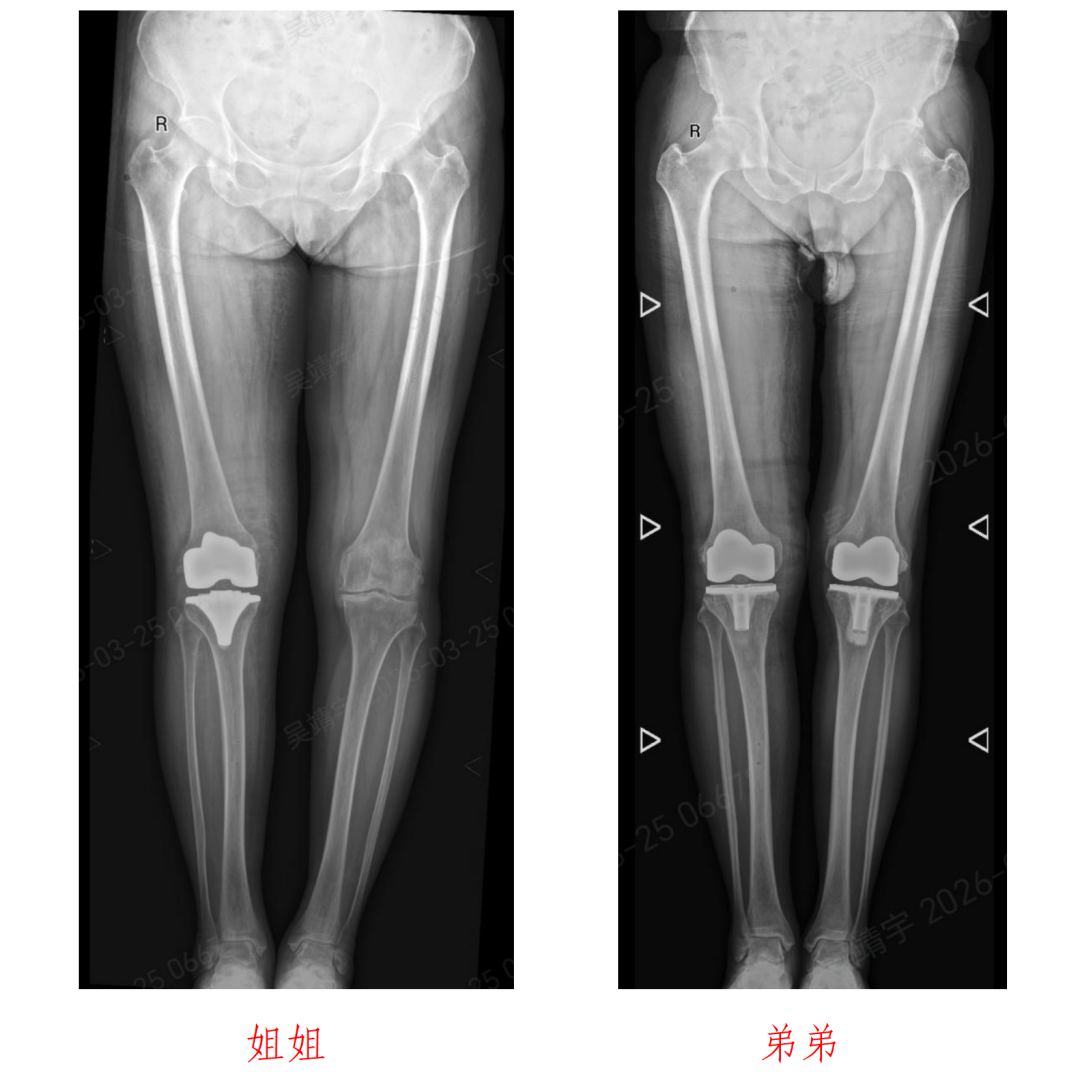

72岁的姐姐沙女士与64岁的弟弟沙先生,多年饱受膝关节病痛困扰。

近日,北京积水潭医院郑州医院关节外科主任杨锴、副主任医师吴靖宇采用骨科手术机器人辅助全膝关节置换术,成功为这对姐弟患者实施右侧人工全膝关节置换手术。

沙女士姐弟二人多年来均被严重的膝关节骨性关节炎困扰,膝关节疼痛、肿胀、活动受限,日常行走、上下楼梯都十分困难,严重影响生活质量。随着年龄增长,病情愈发严重,保守治疗早已无法缓解症状,都希望可以使用手术改善生活质量。